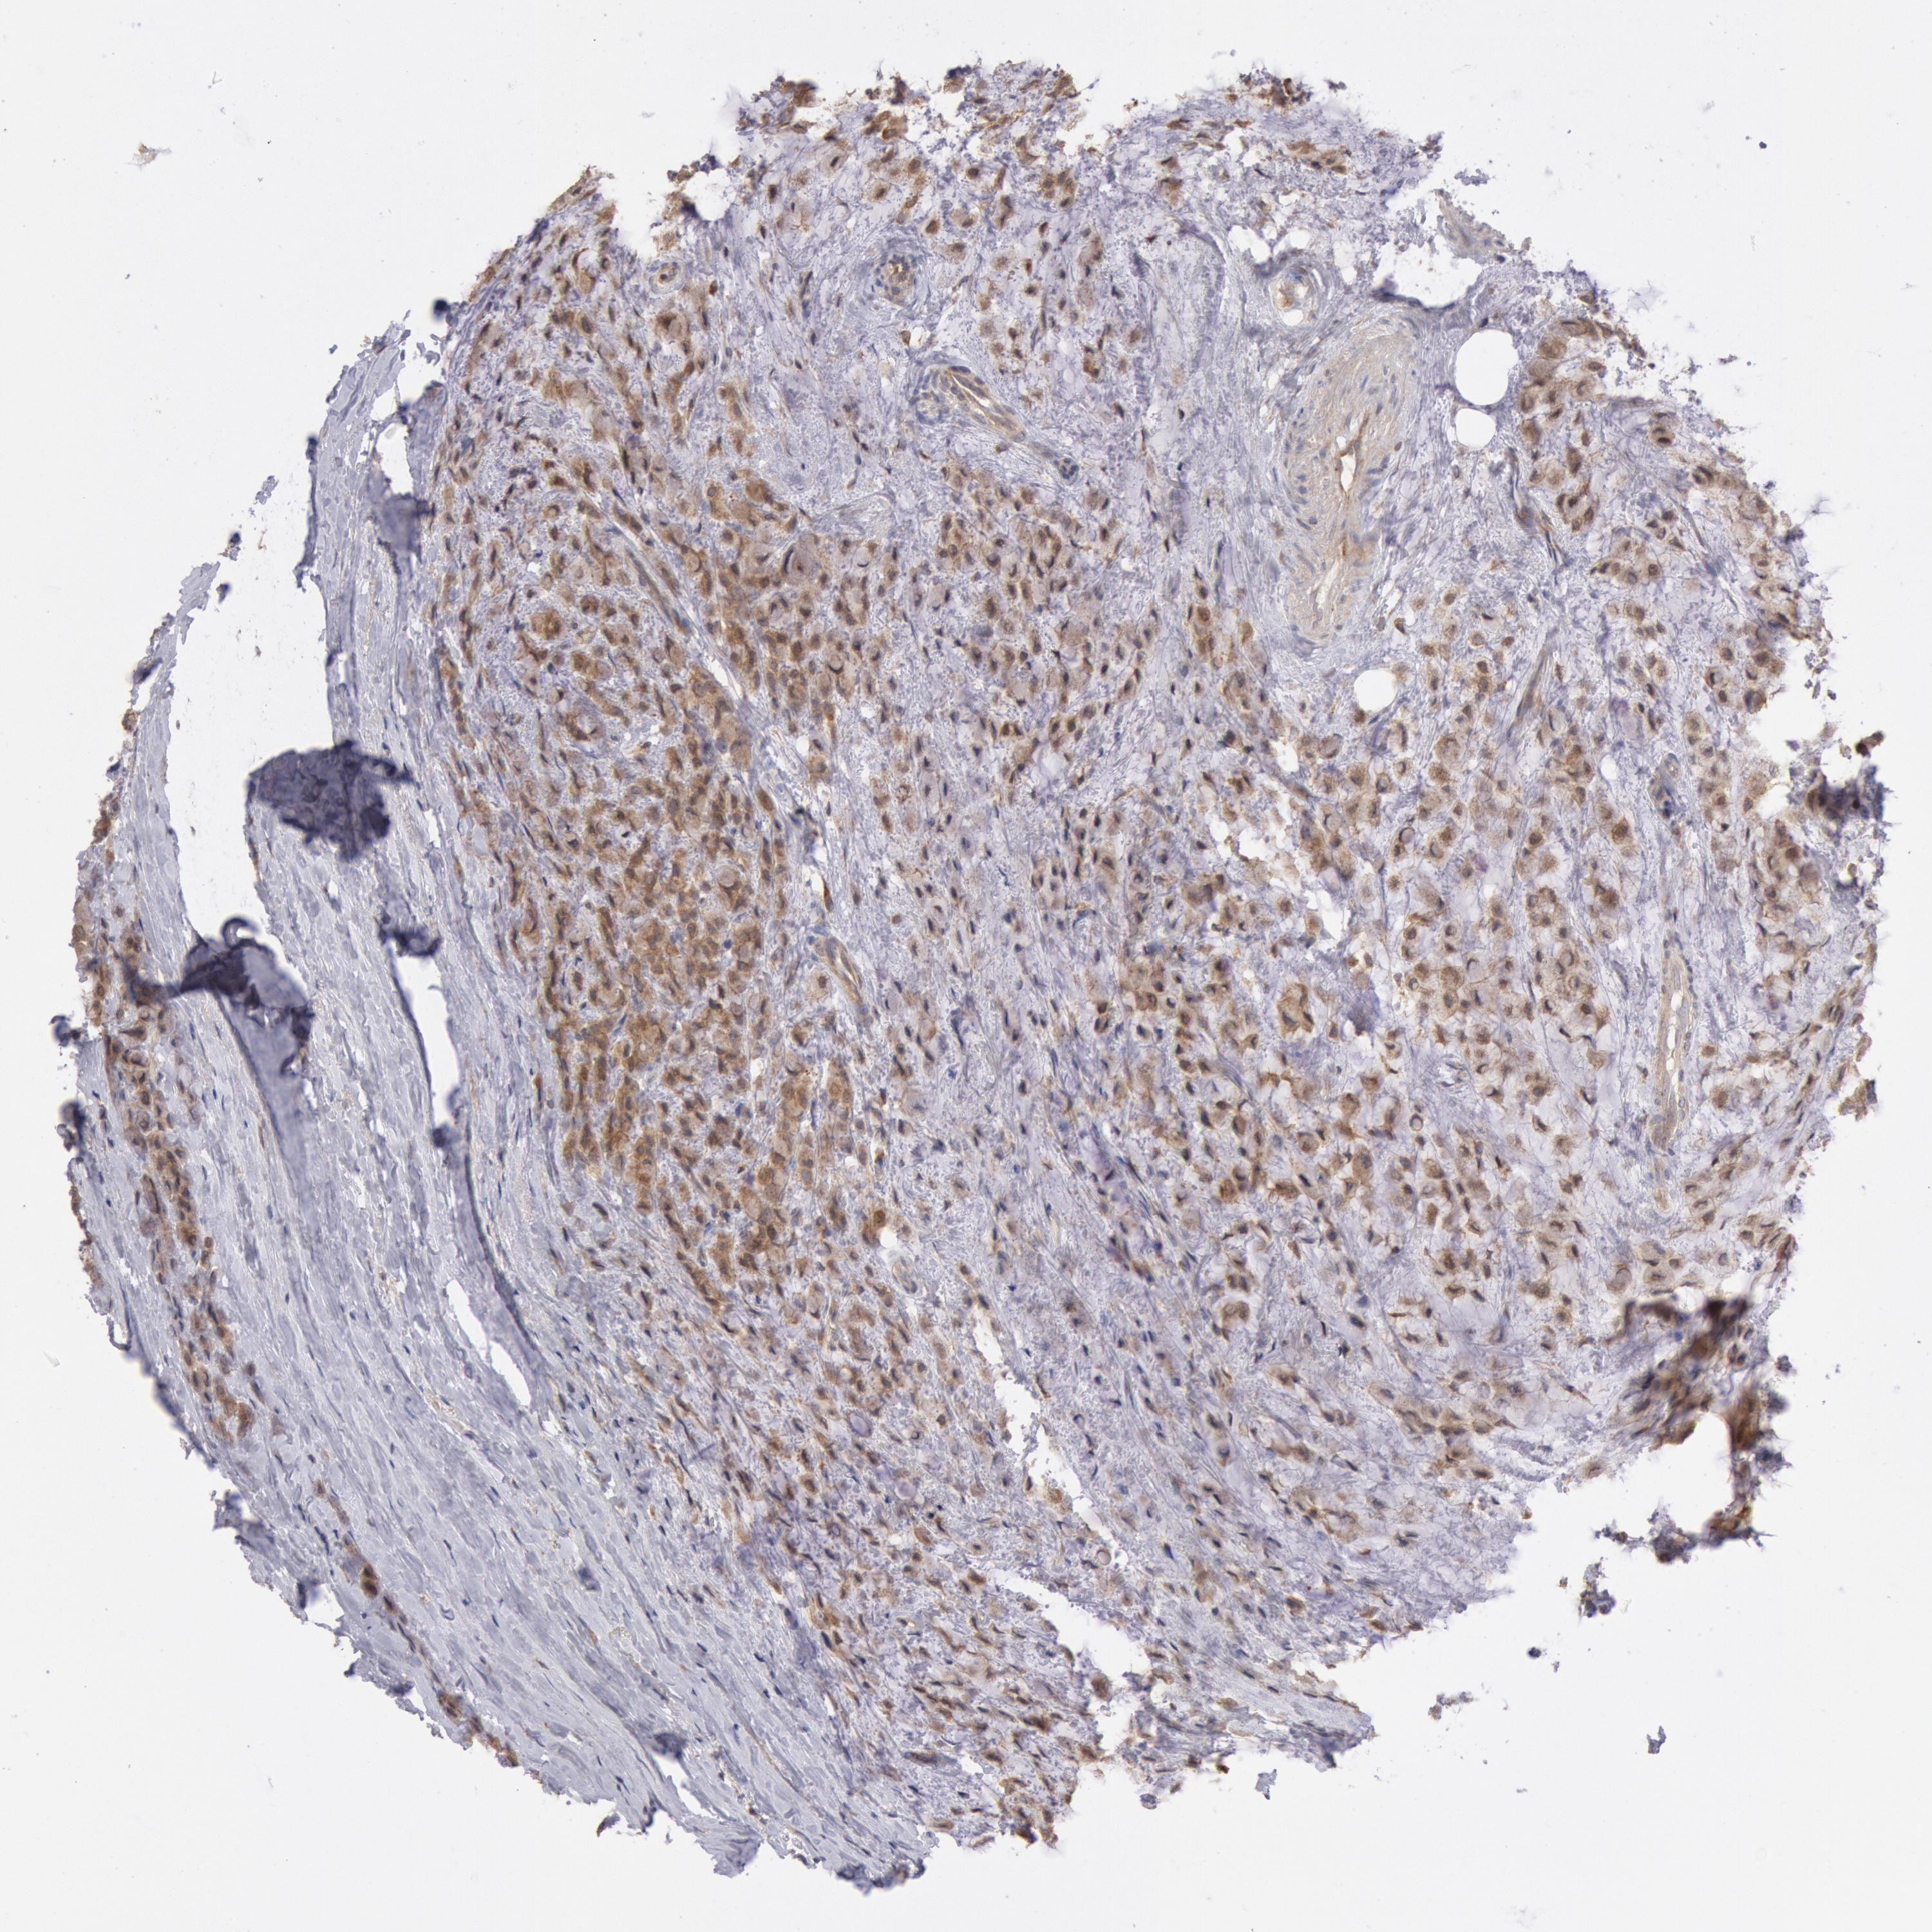

BRCA TCGA BRCA VALIDATION PROTEIN EXPRESSION